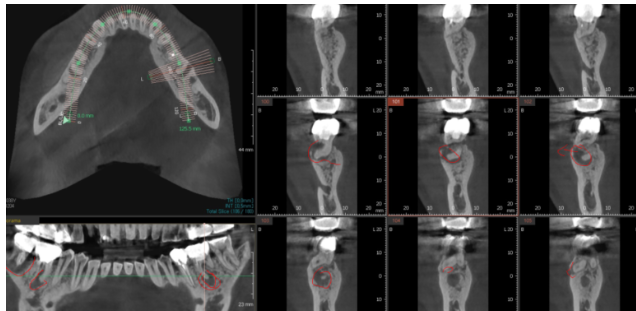

231204

ct를 찍어 본 것인데

빨간색 동그라미 친 부분이

뼈가 다 녹은 부분입니다.

까맣죠~?